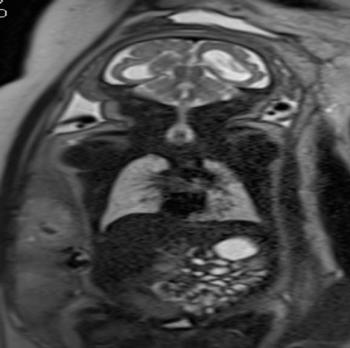

In a third study, ultrasound and fetal MRI were performed on pregnant patients with Zika virus infection at different gestational ages. Once the babies were born, they underwent ultrasound, CT and MRI. The researchers then created 3-D virtual and physical models of the skulls. More than half the babies had microcephaly, brain calcifications and loss of brain tissue volume, along with other structural changes.

"The emergence of Zika virus in the Americas has coincided with increased reports of babies born with microcephaly," said study author Heron Werner Jr., M.D., Ph.D., from the Department of Radiology at Clínica de Diagnóstico por Imagem. "An early diagnosis may help in treating these babies after birth. Moreover, the knowledge of abnormalities present in the central nervous system may give hints about the pathophysiology of the disease."